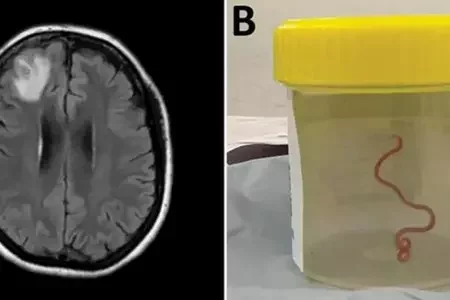

В Австралии женщина долгое время жаловалась на депрессию и проблемы с памятью. В ее мозгу нашли живого червя3